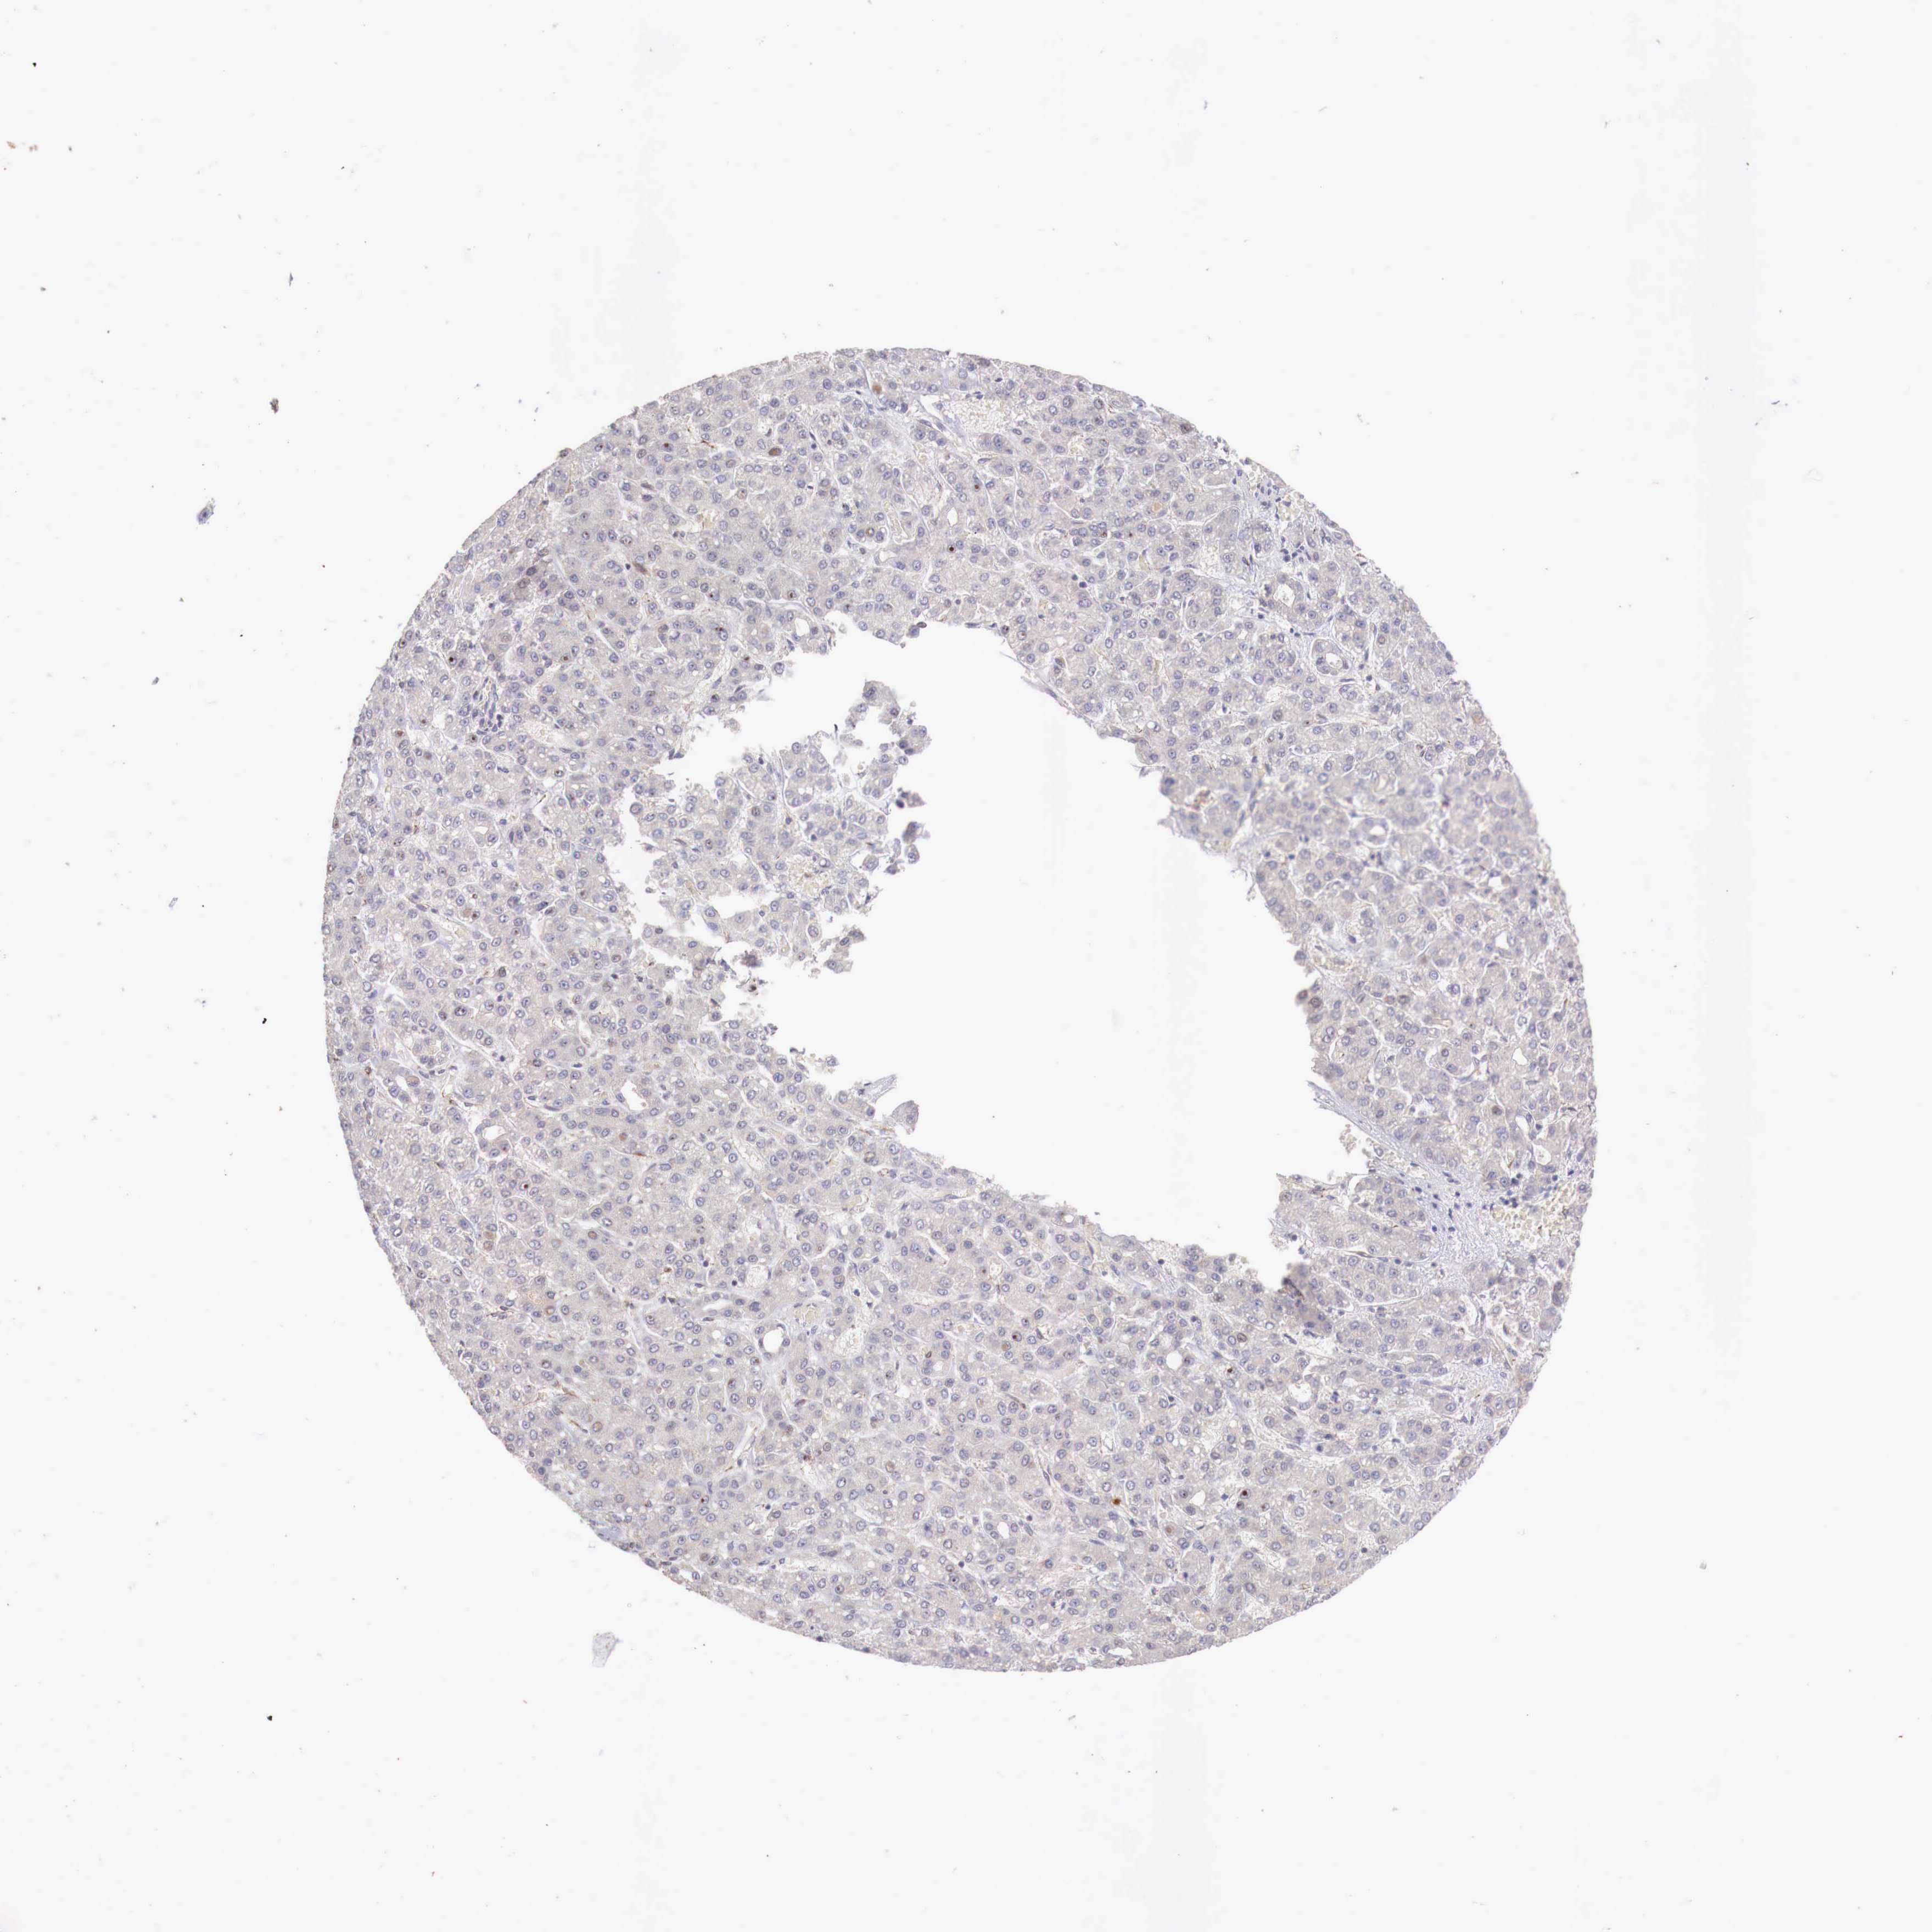

LIVER CANCER - Protein expressioni

A mouse-over function shows sample information and annotation data. Click on an image to view it in a full screen mode. Samples can be filtered based on level of antibody staining by selecting one or several of the following categories: high, medium, low and not detected. The assay and annotation is described here.

Note that samples used for immunohistochemistry by the Human Protein Atlas do not correspond to samples in the TCGA dataset.

Antibody stainingi

Antibody staining in the annotated cell types in the current human tissue is reported as not detected, low, medium, or high, based on conventional immunohistochemistry profiling in selected tissues. This score is based on the combination of the staining intensity and fraction of stained cells.

Each image is clickable and will lead to virtual microscopy that enables deeper exploration of all samples and also displays staining intensity scores, fraction scores and subcellular localization as well as patient and tissue information for each sample.

Antibody CAB000327

Staining

High

Medium

Low

Not detected

Intensity

Strong

Moderate

Weak

Negative

Quantity

>75%

75%-25%

<25%

None

Location

Nuclear

Cytoplasmic/membranous

Cytoplasmic/membranous,nuclear

Carcinoma, Hepatocellular, NOS

Cholangiocarcinoma